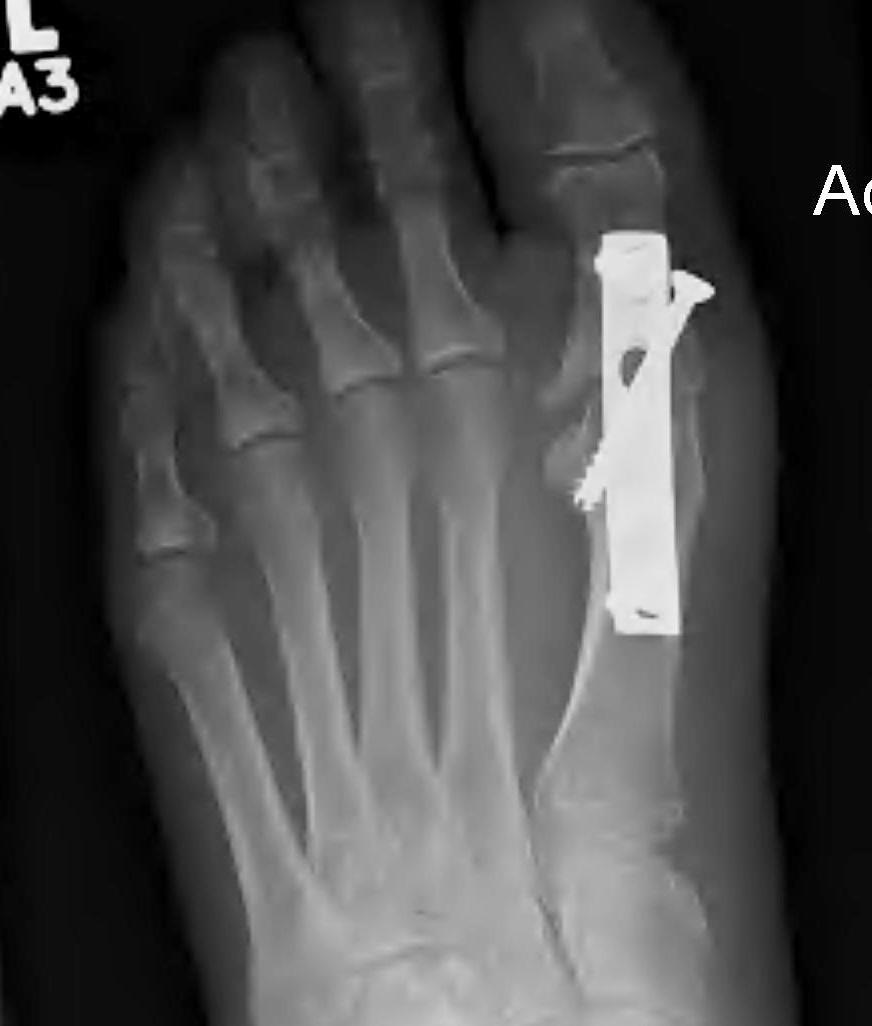

Plate fixation

Screw + plate fixation

Fixation

- screws / plate / screws + plate

- 4 year follow up of 60 1st MTPJ fusion

- screw + plate

- 93% fusion

- remainder painless pseudoarthrosis

- 72% very satisfied, 18% satisfied